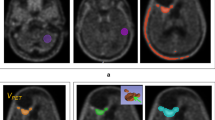

SPECT was started 30 min after intravenous injection of 150 MBq 201Tl-chloride, using a dual-head gamma camera (ECAM, Siemens, Chicago, IL). Projection data were acquired with a 64 × 64 matrix, 60 s per projection. Images were reconstructed with a Hanning filter (cut-off frequency, 0.56 cycles/cm), without attenuation correction. Previously validated maximal tumor intensity was defined as the ratio of the mean tumor counts in the axial slice with the maximal tumor activity and the mean activity in the contralateral supratentorial cerebral hemisphere, and expressed as tumor–nontumor ratio (TNT) (Fig. 1) [25, 27]. Based on this definition, the maximal intensity of normal brain tissue is one, and accordingly, in case no tumor activity is detected by 201Tl SPECT, TNT is one.

Manual region of interest (ROI) definition technique: focally enhanced uptake in a left-sided glioma, showing the axial slice with the maximal tumor uptake. Typical manually drawn ROI displayed around the tumor (plus sign), the contralateral hemisphere (A), its contralateral mirror (B) and the scalp (C)

Figure 2 demonstrates SPECT images of two patients with respectively high (TNT 3.1, Fig. 2a) and low (TNT 1.4, Fig. 2b) 201Tl uptake, with corresponding T1-weighted post-gadolinium MR images representing the two largest perpendicular transverse enhancing tumor diameters (in Fig. 2a only the enhancing area with residual tumor postoperatively was calculated).

SPECT images of two patients with respectively high (TNT, 3.1) (a) and low (TNT, 1.4) (b) 201Tl uptake in right frontal, respectively, left parietotemporal localized tumor, with corresponding T1-weighted post-gadolinium MR images representing the two largest perpendicular transverse enhancing tumor diameters (in (a), only the enhancing area with residual tumor postoperatively was calculated)